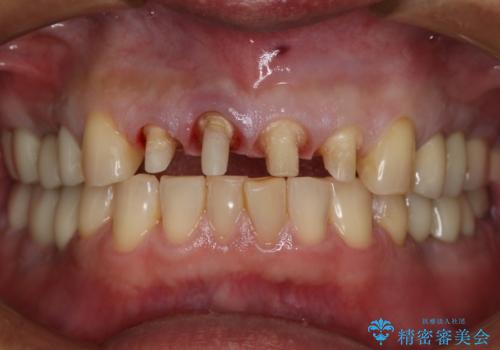

前歯の被せ物をリニューアル

- 上の前歯の正中離開と色味の不満を主訴にご来院されました。

神経を取っている右上2番目の歯は根尖部に病巣があったため根管治療をした上で土台を立て、被せ物の作製を行いました。右上1番目の歯は他院にてとても大きく深い金属の土台が入れられており被せ物の色調に影響を与えていましたが、すべて取りきることのリスクが高いため途中まで除去し目立ちにくいファイバーコアで補強と色調の改善を行いました。